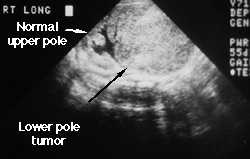

Shortly after birth, this infant was found to have a right upper quadrant mass. This ultrasound shows a large solid tumor in the lower pole of the kidney. Notice how many echoes are generated by the mass (it is light gray). You can see a slightly dilated renal pelvis at the upper pole of the kidney. The tumor obstructed the ureter causing hydronephrosis. This is a mesoblastic nephroma. They are almost always benign. The tumor was removed and the girl is doing well.